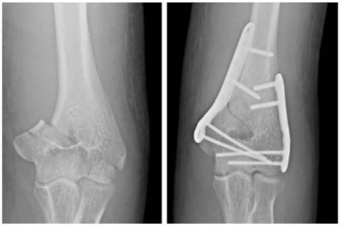

Um paciente de 30 anos de idade foi vítima de queda de árvore há cerca de um dia, sofrendo trauma no cotovelo esquerdo. Foi atendido no pronto-socorro e solicitadas as radiografias retratadas nas figuras.

O processo de consolidação óssea ocorre do(a)

Considerando o princípio utilizado, espera-se que a consolidação obtida seja

No referido caso clínico, para estabilização absoluta, foi utilizada a compressão interfragmentária usando parafuso

No acesso cirúrgico lateral ao úmero distal, o nervo radial está localizado entre o músculo

Assinale a alternativa que indica a principal ação do músculo braquial.

O músculo braquial é inervado pelos nervos

A inserção do músculo braquial ocorre na(o)

No úmero, o músculo braquial tem origem nos dois terços

No acesso cirúrgico posterior para o tratamento dessa fratura, a estrutura anatômica que deve ser dissecada e afastada para evitar sua tração é o nervo

De acordo com a classificação AO, trata-se de uma fratura